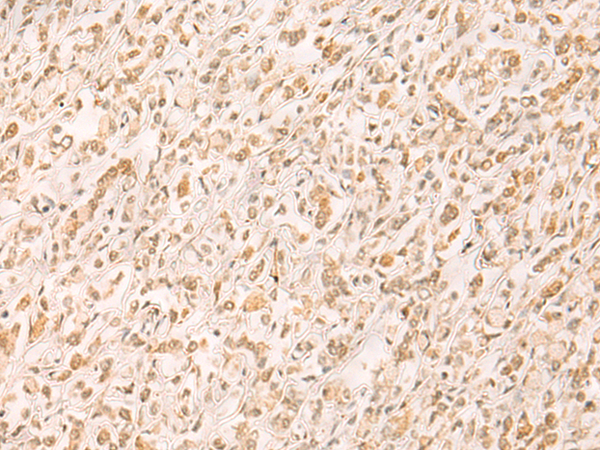

IHC positive control: |

Human gastric cancer and Human esophagus cancer |